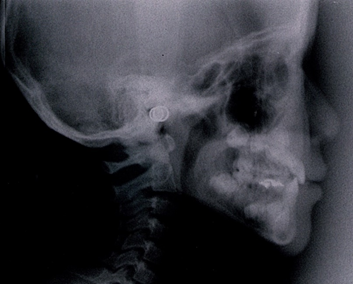

次に骨格で比べてみましょう。

同じ患者様の矯正治療終了後の骨格です。

不安定に見えていた咬み合わせが、反対咬合が改善されて安定して咬みあっていることが分かります。小学校低学年の治療であれば早期治療により反対咬合は容易に改善可能で、骨格の変化を考えてみても反対咬合は早期治療の効果が得られやすい症例と言えます。

次に骨格で比べて診ましょう。

7歳 初診時 女子の受け口の骨格

7歳 治療終了時 女子の受け口の骨格です。

同じ人の1年後の骨格です。

小学校低学年の治療であれば、この変化は普通に起こる変化です。

骨格のことからも受け口は早期治療の効果が得られやすい症例です。